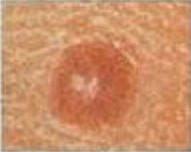

皮肤检查 我们的主要目标是早期发现皮肤癌。通过使用特殊的皮肤显微镜和一种称为皮肤镜检查的技术,我们可以观察皮肤表面和深层组织,从而帮助我们评估可疑的痣或皮肤病变。皮肤镜检查提高了早期发现黑色素瘤的几率。 第二个目标是提高诊断的特异性。皮肤镜检查的特异性可达 85%,有助于避免不必要地切除最终证实为良性的痣和皮肤病变。 周二上午 10 点至 12 点,杰克逊法院诊所。 务必预约。 每次预约 20 分钟。 持有效医保卡,自费 $80。 手术费用自费 $100。 皮肤癌和癌前病变的类型 Melanoma黑色素瘤Basal Cell Carcinoma基底细胞癌Squamous Cell Carinoma鳞状细胞癌Actinic Keratosis光化性角化病Atypical Mole非典型痣Merkel Cell Carcinoma默克尔细胞癌 普通的 黑色素瘤 A 不对称 对称的 不对称 B 边界 边界均匀 边界不均匀 C 颜色 单色 多种颜色 D 直径 小于 1/4 英寸 大于 1/4 英寸 E 不断演变 普通痣 尺寸、形状和颜色发生变化 返回 患者须知(我们的服务)